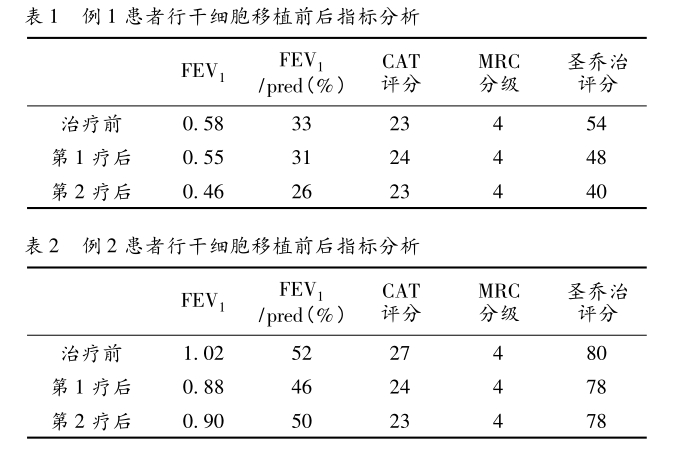

統(tǒng)計(jì)分析結(jié)果從表1、表2可看出對(duì)比治療前后的傳統(tǒng)肺功能檢查提示 FEV1 、FEV1 /pred( % ) 指標(biāo)無(wú)明顯好轉(zhuǎn),而生活質(zhì)量評(píng)分較治療前改善。

從表3、表4提示,CT 值在-1000 至-951 比例有所下降,Class4( % ) 亦明顯下降,故肺氣腫較治療前好轉(zhuǎn)。

綜上所述,研究中有2例慢性阻塞性肺疾病在應(yīng)用重組人粒細(xì)胞集落刺激因子動(dòng)員干細(xì)胞治療2~3周期后,三維CT測(cè)量肺功能指標(biāo)有所改善。

結(jié)論:重組人粒細(xì)胞集落刺激因子動(dòng)員干細(xì)胞治療慢性阻塞性肺疾病是一種安全有效的方法,值得臨床推廣。